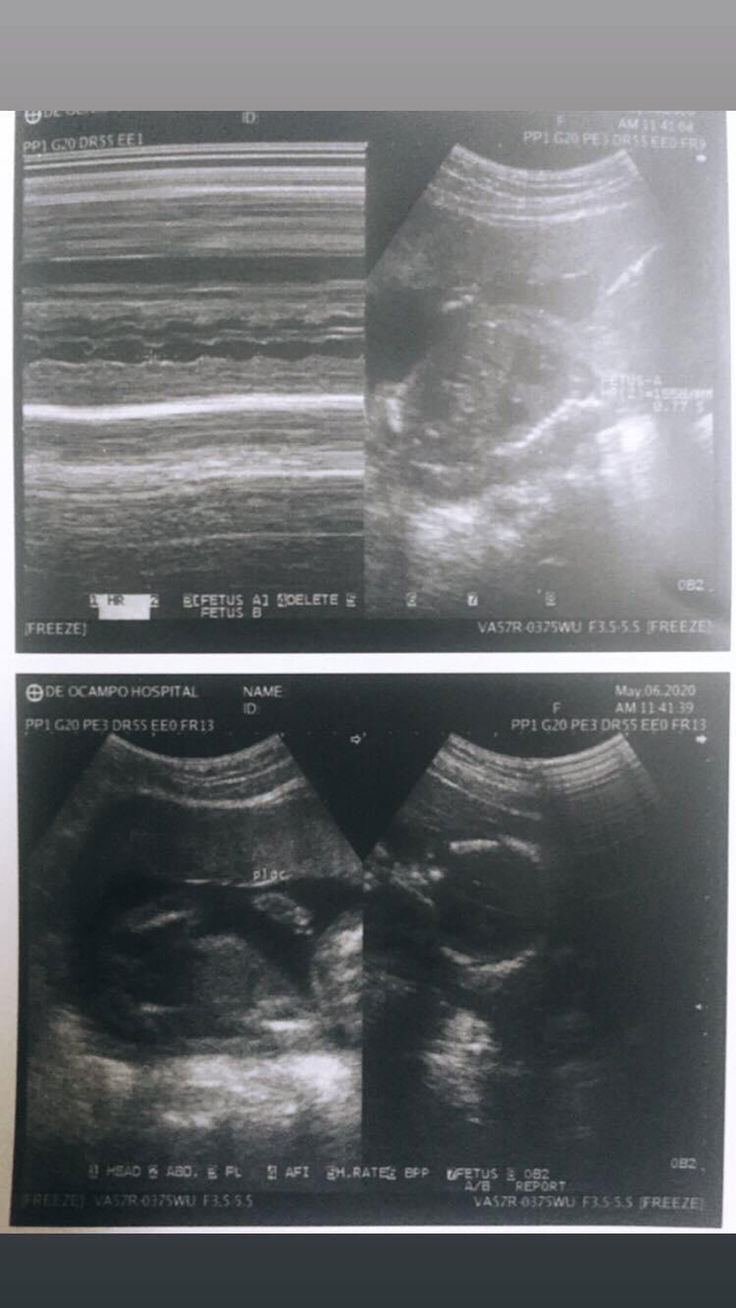

BABY GIRL o BABY BOY?

Sabi ng Doctor pinapakita naman raw ni baby gender niya. Hindi niya lang matukoy kasi outdated ang gamit niya. Sa tingin niyo mga mommies? Turning 24weeks. TIA

parang baby girl po, check ang 3rd pic parang may hiwa sa gitna parang ganyan din po kasi ultrasound ko medyo malabo lang 😁

BABY BOY OR BABY GIRL?

Sabi ng Doctor, hindi naman raw hinahide ni baby yung gender niya. Hindi niya lang raw matukoy kasi outdated yung gamit niya. Sa tingin niyo mga mommies? TIA :)

hindi kita